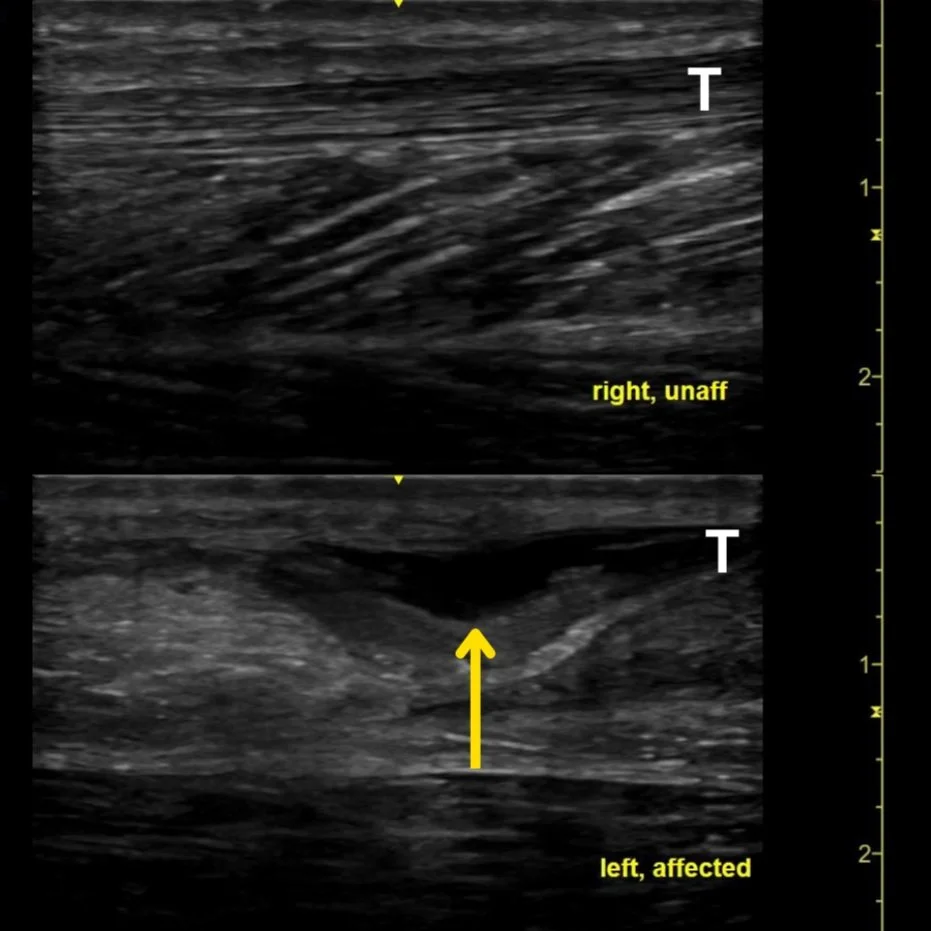

Figure 2: Ultrasound of the bilateral Achilles tendon with the affected side observing a collection of anechoic fluid (yellow arrow) adjacent to tendinous structure with distorted anatomy compared to unaffected side.

While this test has a reported sensitivity and specificity of 96% and 98%, respectively, there can be obstacles causing an up to 10% missed diagnosis rate when the test is negative. For example, suppose there is a significant amount of swelling. In that case, if the patient is guarding due to pain or if the patient has a larger body habitus, it may be difficult to correctly perform the exam and see the presence or absence of plantarflexion. Plain films do not typically aid in the diagnosis other than to look for any fractures. However, an easy, cost-effective, and radiation-free tool to have at the bedside to aid in this diagnosis is ultrasound. To further clinch the diagnosis, combining these two tools utilizing the Realtime Achilles Ultrasound Thompson (RAUT) test would allow you to visualize with ultrasonography the (lack of) Achilles movement while squeezing the gastrocnemius muscle if there was any discrepancy. Disruption in the tendon with surrounding edema suggests tendon rupture (Figures 1 and 2). Regarding management, the patient should be placed in a splint with the affected ankle in slight plantarflexion (20 degrees), instructed to remain non-weight bearing, and follow up with orthopedics.